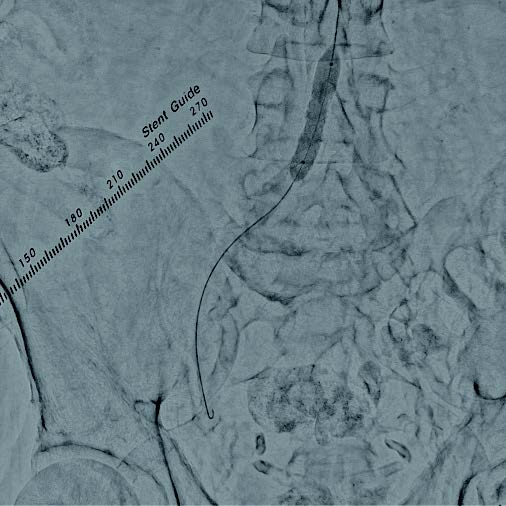

最終造影画像

本症例は総大腿動脈からの順行性穿刺による右膝下動脈の治療を予定していることから、上腕動脈穿刺による腸骨動脈へのEVTを計画した。右上腕動脈から6 Frガイディングシースを用いてアプローチし、術前の下肢血管造影を行った。重症下肢虚血患者であり、安定したinflowの確保が重要と考え、高度石灰化を伴うことおよび血管径が11 mmと大きいことを踏まえ、後拡張の汎用性の高いVBX ステントグラフトを選択する方針とした。0.014 inchガイドワイヤーで病変通過後、6.0 × 40 mmバルーンで前拡張を行った(図1)。ガイドワイヤーを0.035 inchスティッフタイプに変更し、VBX ステントグラフト7 × 39 mmを後拡張での短縮を考慮し、数 mm 程度大動脈に突出させる形で留置した(図 2)。10.0 × 40 mmバルーンで後拡張(図3)を行い、IVUSで解離等がないことを確認し、最終造影で合併症が無いことを確認し手技を終了した。